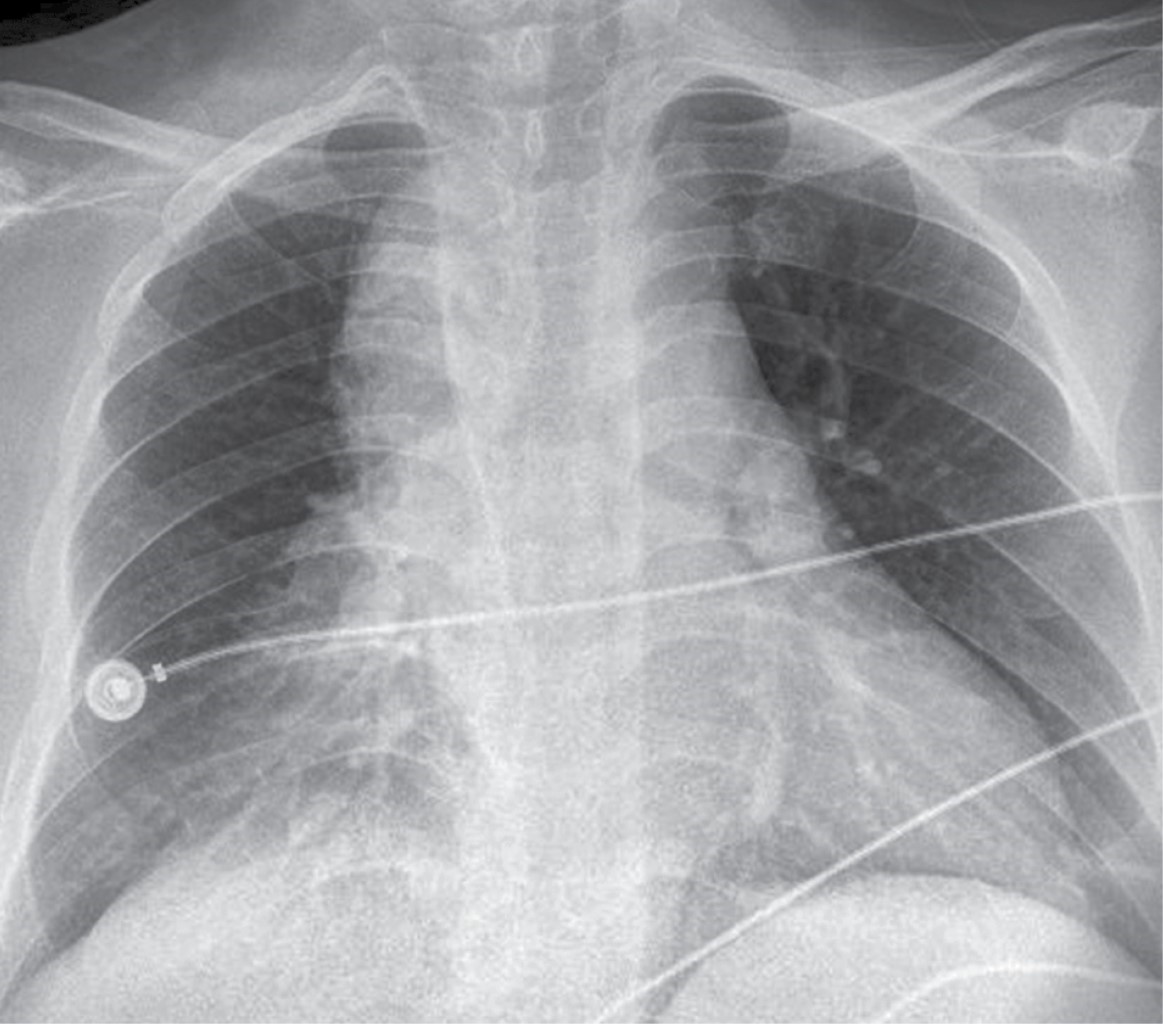

Imaging studies' role is vital in diagnosis, without neglecting a thorough clinical history and physical examination. The main findings in the plain chest x-ray raise the suspicion of DNM and the clinical signs and symptoms of severe infection associated with a history of cervical, dental, or oropharyngeal infection. Said radiological findings can be widening of the mediastinum, pneumomediastinum, mediastinal hydro-aerial levels, anterior displacement of the tracheal air column due to a prevertebral opacity of the soft tissues, enlargement of the cardiac silhouette and loss of the normal lordosis of the cervical spine, as well as unilateral or bilateral pleural effusion.9,10,12 Cervicothoracic computed tomography (CT) should be performed immediately, as CT of the chest and neck can reveal detailed information regarding the extent of the necrosis process and suggests, within the framework of the surgical treatment approach, the best tactic for effective drainage to optimize the best post-surgical outcome for the patient and with it the need for fewer reinterventions.9,10,13-17

In our series, chest radiography continues to be the initial study in all patients with respiratory problems due to its accessibility and quick results (Figure 1); however, chest tomography continues to be the gold standard at our institution for the diagnosis and planning of surgical management in those with mediastinitis (Figure 2).